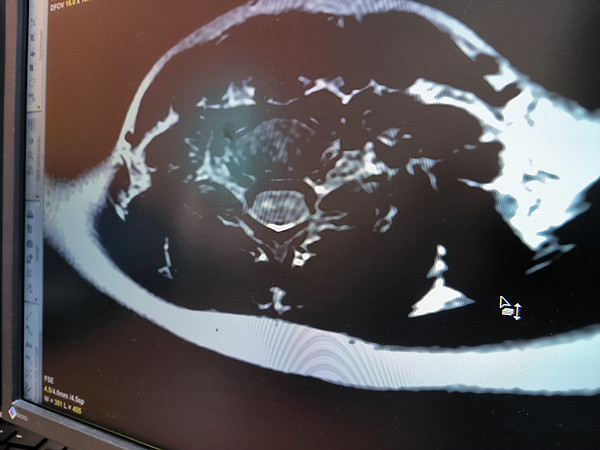

IMG_20230823_133046.